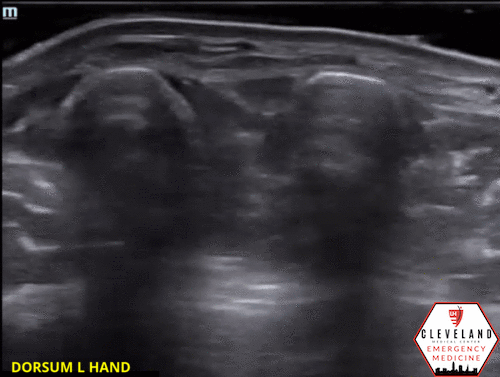

2nd-4th Extensor Tendons with fluid in the tendon sheath

Moving more proximally, the tendons converge at the wrist.

POCUS findings: fluid in the tendon sheath surrounding the extensor tendons along with thickening and mild cobblestoning of the overlying soft tissues. No abscess visualized. Findings suggestive of extensor tenosynovitis.